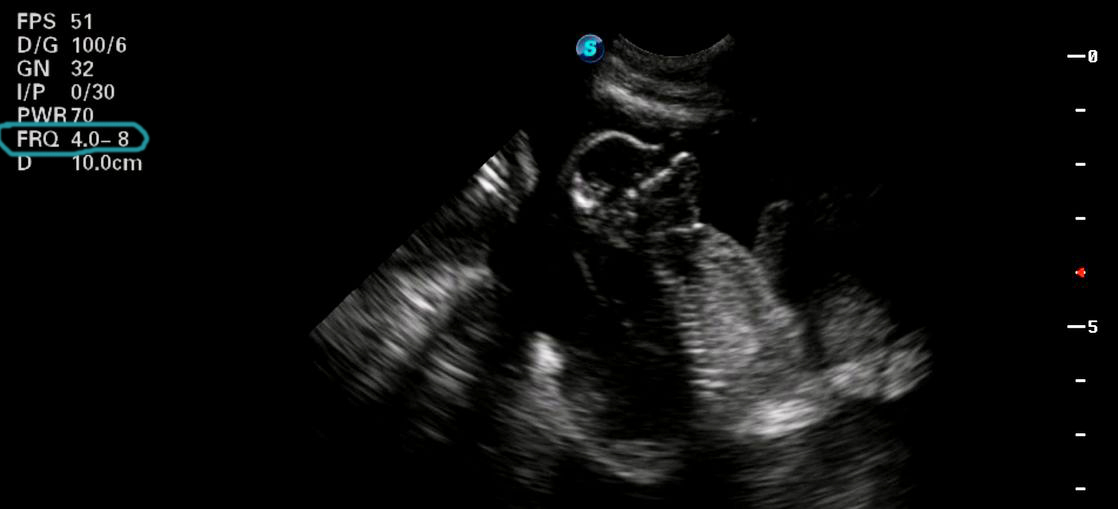

Below are some examples of scan images taken at higher frequencies. The scanning frequency has been circled in blue. The below images are captured at high resolution.

Bulldog ultrasound scan